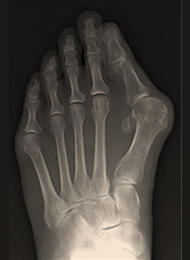

外反母趾

外反母趾とは、足の親指(母趾)が、第2趾の方へ曲がって変形している足の変形です。母趾の付け根の内側の痛みを生じる場合が多く、バニオンと呼ばれる胼胝(たこ)を形成することもあります。親指の症状だけでなく、第2趾や第3趾の足底痛や足の甲の痛みを生じることもあります。靴の調整や足底挿板による治療が基本となりますが、変形の矯正のためには母趾の中足骨を骨切りする手術が必要になる場合があります。

外反母趾の手術法は100種類以上あるといわれていますが、当院では患者さんへの侵襲の少ないDLMO(デルモ)法という第1中足骨遠位骨切り術を行っています。この術式は約2cmの皮膚切開で、第1中足骨を骨頭基部で骨切りしたのち、骨片間を鋼線1本で止めるというシンプルな術式です。この鋼線は手術後1か月で抜去するので、術後に体の中にインプラント(金属)が残らないこともこの術式の特徴といえます。

当院は、DLMO法の第1人者である須田康文医師のもとで研修を積んだ竹島憲一郎医師が執刀を担当しており、多くの患者さんの治療を行っています。

![]() 術前 |

![]() 術直後 |

![]() 術後1年 |